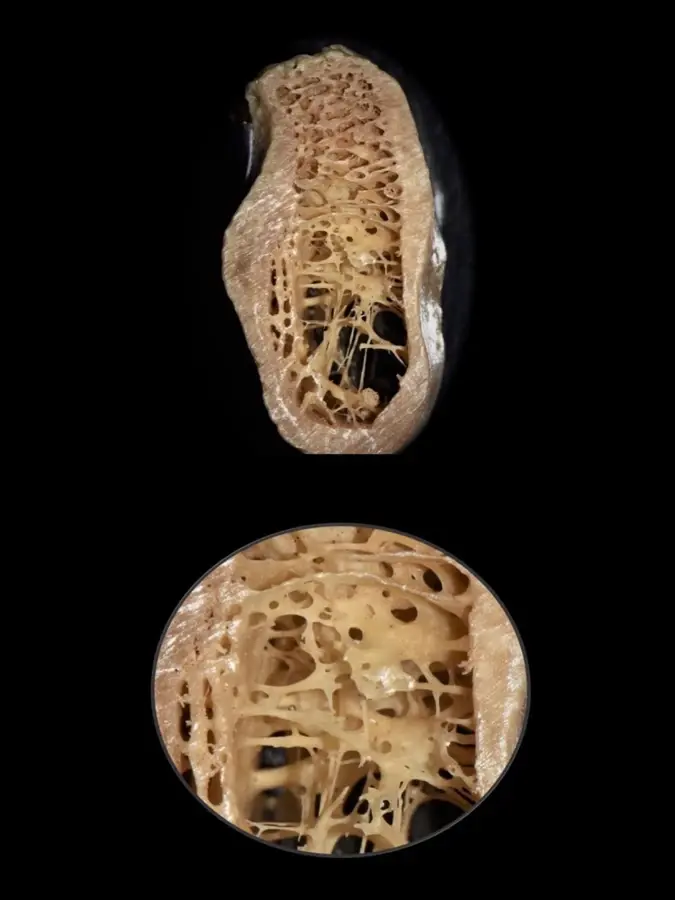

La menor lesividad de los tejidos favorece a la biología ósea y es la razón de que el sistema piezoeléctrico se haya convertido en una elección segura y predecible.

Una reciente publicación de estudios con CBCT propone una modificación a lo anteriormente propuesto por Lekholm y Zarb, que permite sugerir su aplicabilidad para distinguir entre las diversas combinaciones de hueso cortical y esponjoso para definir adecuadamente el tratamiento a fin de optimizar los resultados.17 Esta propuesta se basa en la evaluación de la calidad ósea respecto al grosor de la cortical y a la visibilidad de la cantidad de trabéculas y el tamaño de los espacios medulares en el hueso esponjoso (Figura 4):

- Tipo I: Hueso cortical predominante que rodea al hueso esponjoso de cantidad escasa con trabéculas nítidas en toda la imagen y presencia de espacios medulares pequeños y visibles.

- Tipo II-A: Hueso cortical grueso que rodea al hueso esponjoso de cantidad abundante con trabéculas nítidas en toda la imagen y presencia de espacios medulares pequeños y visibles.

- Tipo II-B: Hueso cortical grueso que rodea al hueso esponjoso de cantidad abundante con predominio de trabéculas difusas en el hueso basal y presencia predominante de espacios medulares amplios y visibles.

- Tipo II-C: Hueso cortical grueso que rodea al hueso esponjoso de cantidad abundante con predominio de trabéculas muy gruesas y nítidas en la basal, con presencia de espacios medulares pequeños y visibles.

- Tipo III-A: Hueso cortical delgado que rodea al hueso esponjoso de cantidad abundante con trabéculas nítidas en toda la imagen y presencia de espacios medulares pequeños y visibles.

- Tipo III-B: Hueso cortical delgado que rodea al hueso esponjoso de cantidad abundante con predominio de trabéculas difusas y presencia de espacios medulares difusos.

- Tipo IV: Hueso cortical difuso que rodea al hueso esponjoso de cantidad abundante con predominio de trabéculas difusas y presencia de espacios medulares difusos.

- Tipo V: Hueso regenerado, de cantidad, visibilidad de las trabéculas y espacios medulares variables.

- Tipo VI: Hueso con patología, de cantidad, visibilidad de las trabéculas y espacios medulares variables.